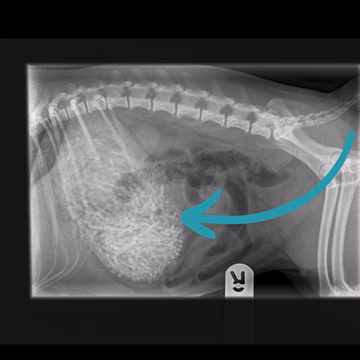

Posnetek iz veterinarske klinike osupnil splet: Takšnega prizora ne vidite pogosto Magazin | 1. okt | 2